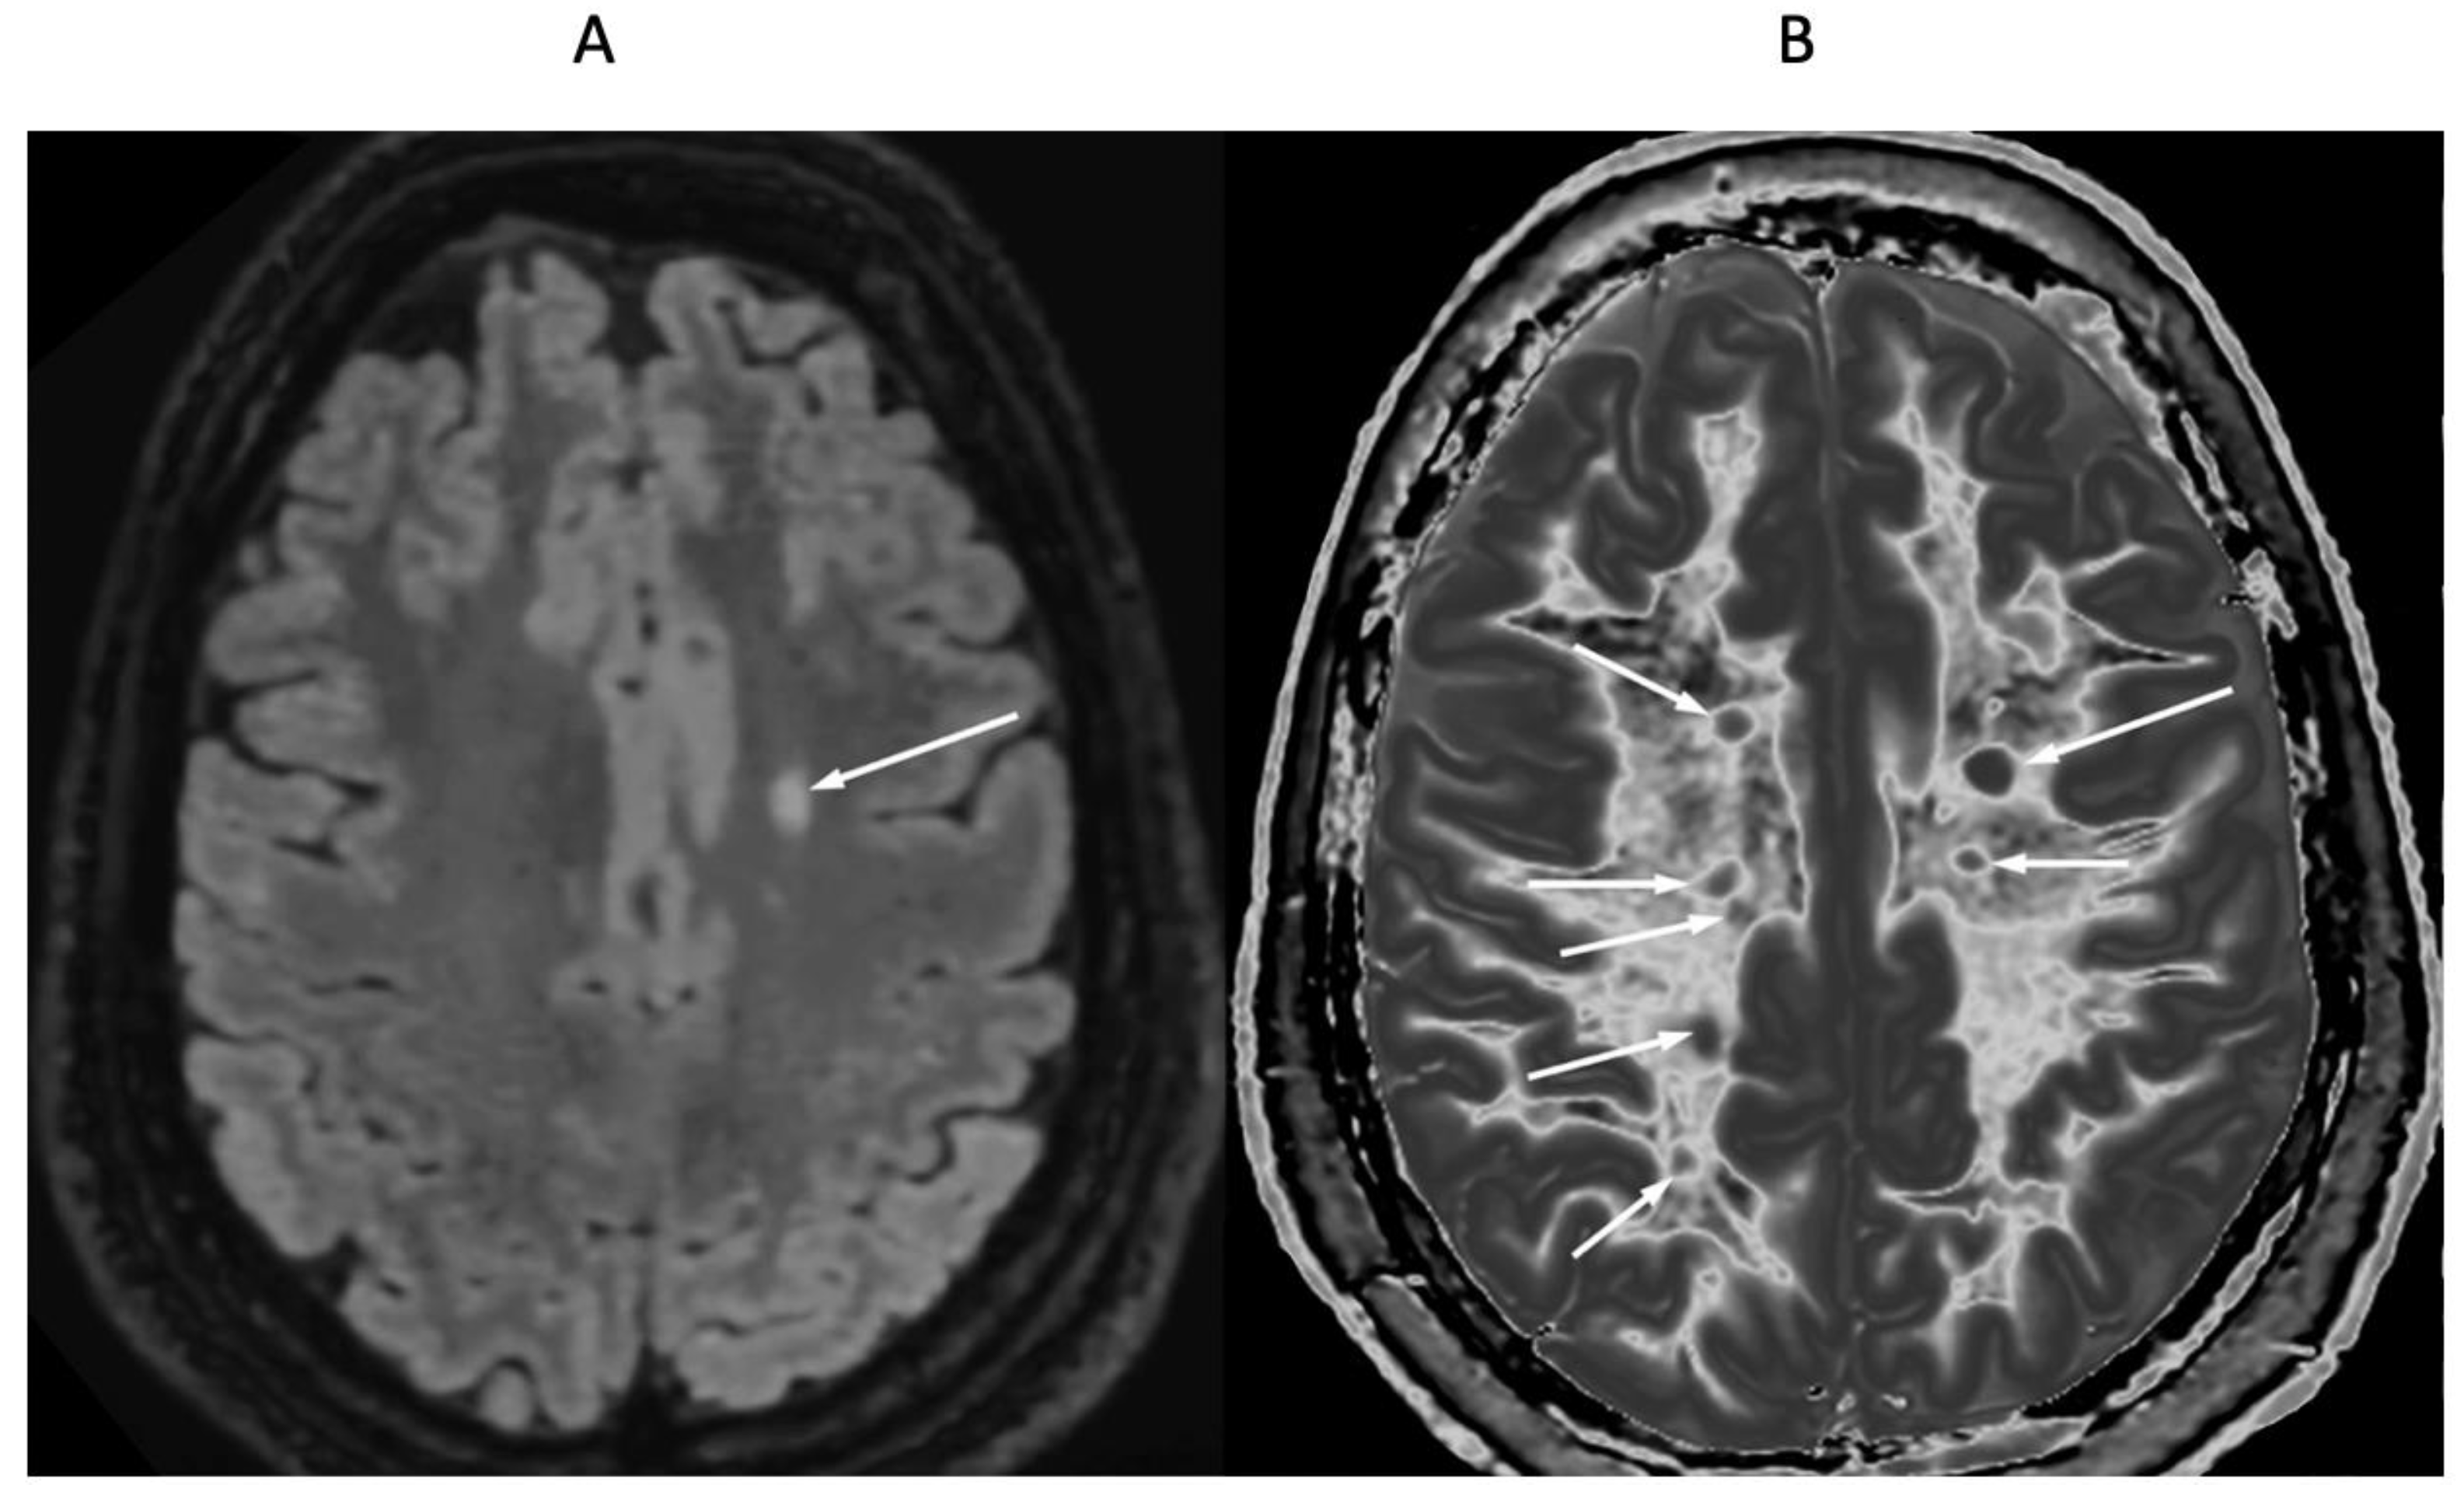

Figure 9 and Figure 10 show a 38-year-old patient with MS in remission (Figure 9A and Figure 10A, left columns) and during a relapse two years and five months later (Figure 9B and Figure 10B, right columns) imaged with the same narrow mD dSIR sequence. Figure 9 shows three positionally matched lower levels in the brain and Figure 10 shows two positionally matched higher levels in the brain. White matter shows a generally low signal during remission (whiteout sign grade 1–2) (Figure 9A and Figure 10A), and a high signal (whiteout sign grade 4–5) during the relapse (Figure 9B and Figure 10B). The multiple levels within the brain show the wide distribution of the high grade whiteout sign in the cerebellar and cerebral hemispheres, as well as in the brainstem. No evidence of a whiteout sign was seen on the corresponding T2-FLAIR images.

Figure 10.

Thirty-eight-year-old female patient with MS in remission (A, left column) and during a relapse (B, right column) two years and five months later (same case as in Figure 9). Matching narrow mD dSIR images at two higher levels in the brain. In remission, white matter shows a low signal (left column). This is increased during the relapse in a bilateral symmetrical distribution consistent with a grade 4–5 (out of 5) whiteout sign (right column). No evidence of a whiteout sign was seen on the T2-FLAIR images.

Figure 11 shows narrow mD dSIR images in a normal adult control (Figure 11A) and in a 77-year-old patient with MS (Figure 11B) during a relapse. In addition to the whiteout sign, there is a loss of contrast between gray and white matter in the thalamus of the patient (Figure 11B). Also, the heads of the caudate nuclei, as well as the insular and peripheral cortices, appear isointense with CSF on the dSIR image. These are grayout signs. No evidence of a whiteout sign or grayout signs was seen on the corresponding T2-FLAIR images.

Figure 11.

Skull-stripped images of a normal control (A) and 77-year-old patient with MS during a relapse (B). There is low signal in the normal white matter in (A) and a whiteout sign in (B). In addition, the gray matter in the thalamus and cortex has a uniform low signal and is nearly isointense with CSF. These are grayout signs. No evidence of a whiteout sign or grayout signs was seen on the positionally matched T2-FLAIR images.